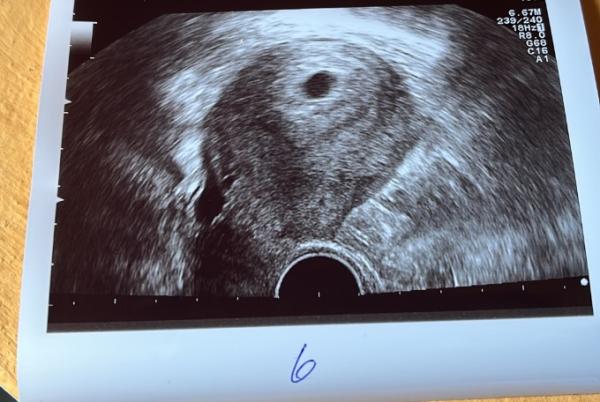

Ultraschall 5+3

Hallo:) Hcg ist zeitgerecht jetzt war ich heute bei 5+3 bei meinem Frauenarzt fruchthöhle war zu sehen aber er konnte den dottersack nicht richtig darstellen. Ist es dafür nicht noch zu früh soll jetzt am Freitag zurück wäre dann bei 6+0 ist das nicht alles viel zu früh ? Ich werde so eng maschig kontrolliert aufgrund der Vorgeschichte zwei FG und eine biochemischeSchwangerschaft. Jetzt hat mich der Termin heute allerdings sehr verunsichert ich pack das Bild mal dazu. Hatte jemand so früh schon einen Ultraschall und wie sahen diese aus. Liebe Grüße

Bild zu Ultraschall 5+3 - Forum für Dezember - Mamis